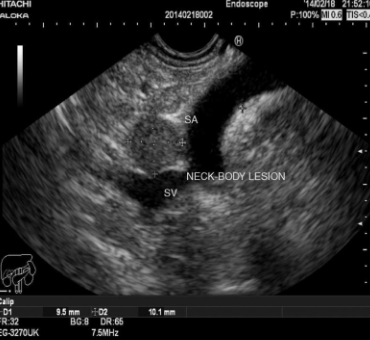

🥉 직장 초음파(EUS)

→ 국소 병기(T·N) 정확히 평가